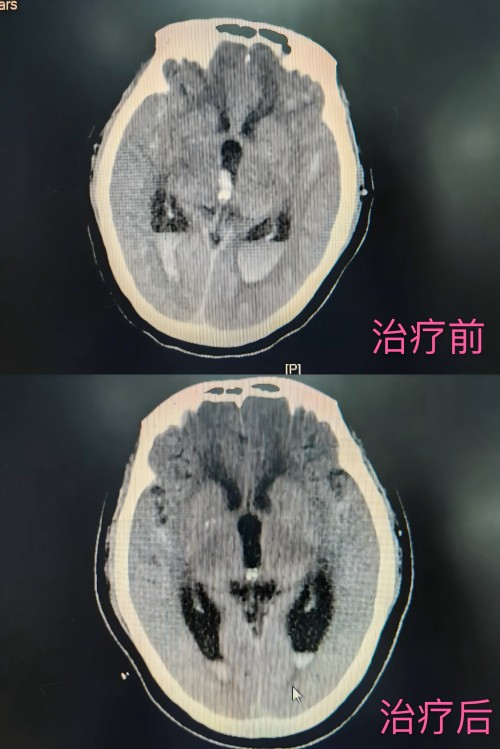

患者治疗前后头部CT对比

据了解,月初患者因头晕3天并一过性意识障碍5小时急诊平车入院,完善头部CT后,结果显示为“蛛网膜下腔出血”。神经介入组为其在全麻下实施了颅内动脉瘤栓塞术,术后在神内监护室进行围手术期管理。该患者当初发病时情况危急,身心承受着巨大痛苦,在医护人员专业且精心的救治下,病情逐渐好转,如今已恢复正常生活,重展笑颜。